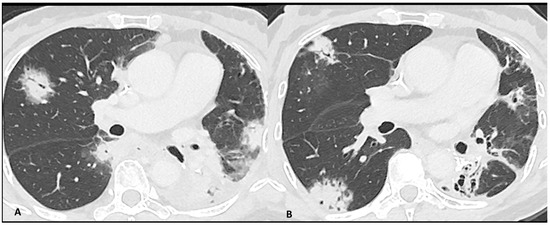

2.2.1. Ir-Pneumonitis

- Pozzessere, C.; Lazor, R.; Jumeau, R.; Peters, S.; Prior, J.O.; Beigelman-Aubry, C. Imaging Features of Pulmonary Immune-related Adverse Events. J. Thorac. Oncol. 2021, 16, 1449–1460. [Google Scholar] [CrossRef]

- Johkoh, T.; Lee, K.S.; Nishino, M.; Travis, W.D.; Ryu, J.H.; Lee, H.Y.; Ryerson, C.J.; Franquet, T.; Bankier, A.A.; Brown, K.K.; et al. Chest CT Diagnosis and Clinical Management of Drug-related Pneumonitis in Patients Receiving Molecular Targeting Agents and Immune Checkpoint Inhibitors: A Position Paper from the Fleischner Society. Radiology 2021, 298, 550–566. [Google Scholar] [CrossRef]

| Pneumonitis | OP | Multifocal, patchy, consolidations or GGOs with peribronchovascular and/or subpleural distribution | Migratory on a subsequent scan | Radiation Pneumonitis Infectious pneumonia Tumor progression |